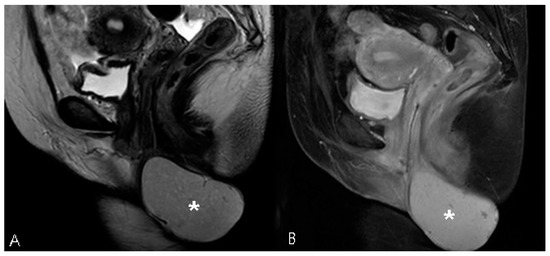

A Huge Hemorrhagic Epidermoid Cyst of the Perineum with Hypoechoic Semisolid Ultrasonographic Feature Mimicking Scar Endometriosis

Nam, G.; Lee, S.R.; Eum, H.R.; Kim, S.H.; Chae, H.D.; Kim, G.J. A Huge Hemorrhagic Epidermoid Cyst of the Perineum with Hypoechoic Semisolid Ultrasonographic Feature Mimicking Scar Endometriosis. Medicina 2021, 57, 276. https://doi.org/10.3390/medicina57030276